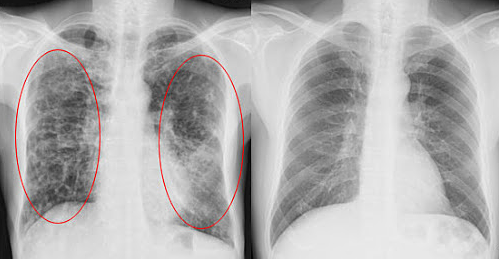

中国工程院院士钟南山就曾提出:“广州人的肺都是黑的,更何况北京!我最担心的还是雾霾会引发肿瘤!”

除了雾霾,生活中还有很多“伤肺”因素!比如吸烟、二手烟、油烟、粉笔灰、车间粉尘等,都会危害我们的呼吸道和肺!

英国著名医学节目《BBC》就曾报导过:一位烟龄20年的老教师,患肺癌晚期去世。医生做病理解剖时发现:“肺部已全部变黑,里面堆满了各种垃圾毐素!”

墨尔本大学临床实验显示:肺部感染者服用澳洲肺清一个月,肺部杂质几乎全部消失,效果非常接近洗肺,但是成本更低,且没有任何痛苦!